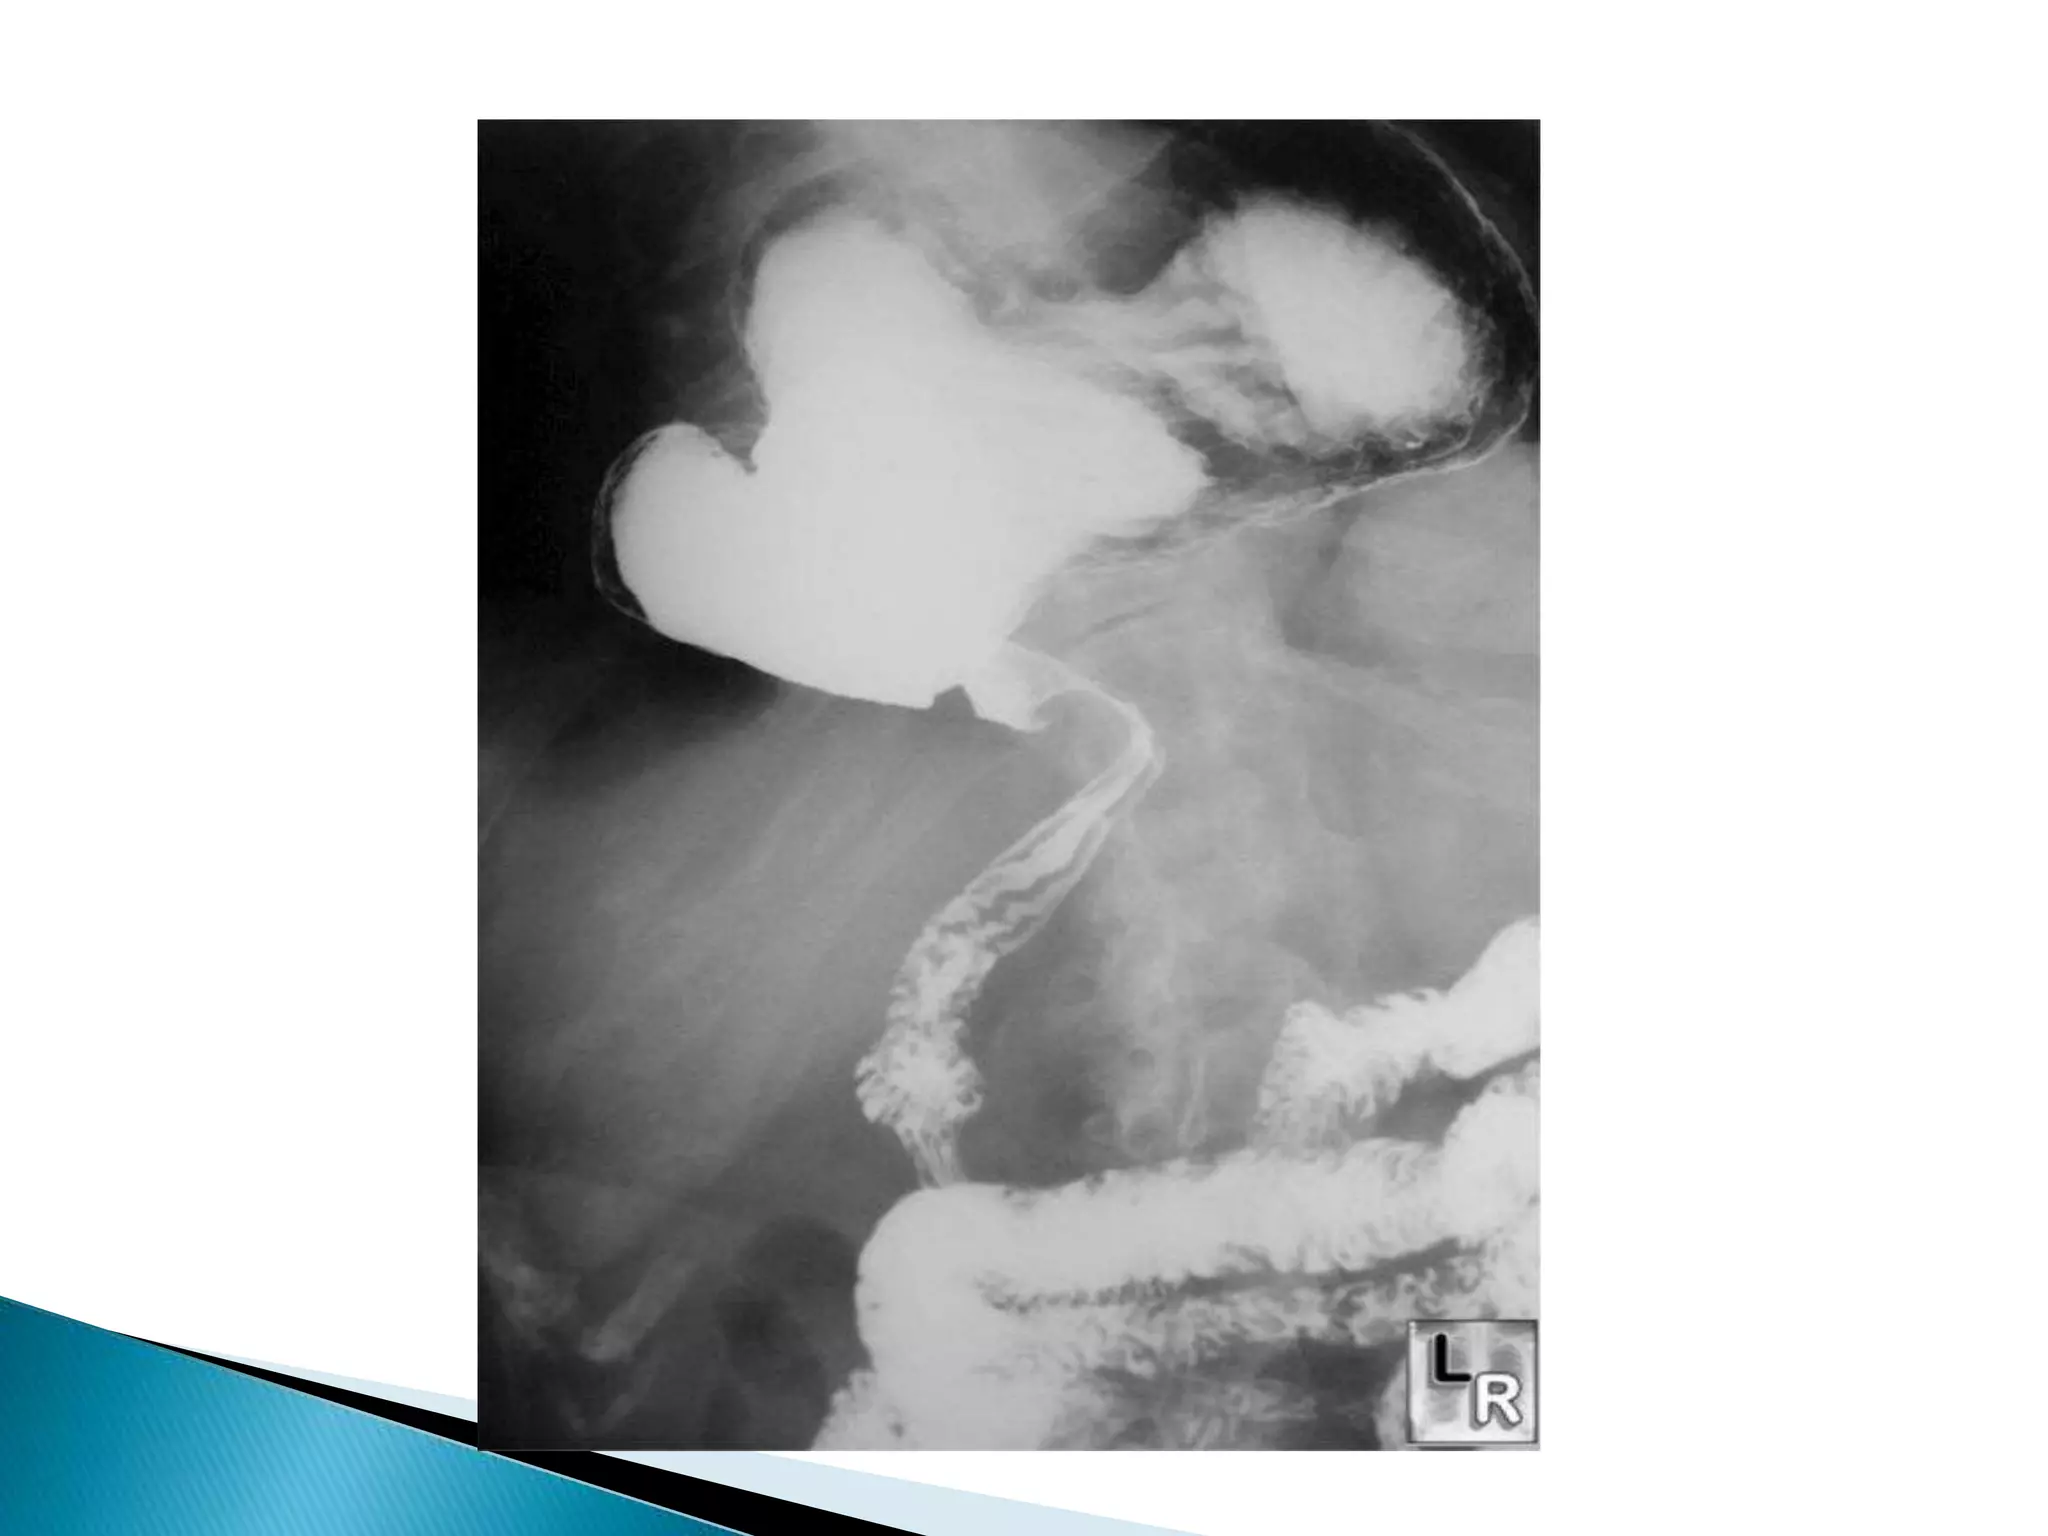

Dilated cecum

Cecum

Contrast

In Descending colon

Barium Enema

Point of Obstruction

Ascending colon

 20 yearold woman presented to the ED with 12 hours of abdominal pain, nausea. and vomiting low grade fever.  No past surgical history  PMH: Polycystic ovarian disease

Barium Enema Point ofObstruction Ascending colon